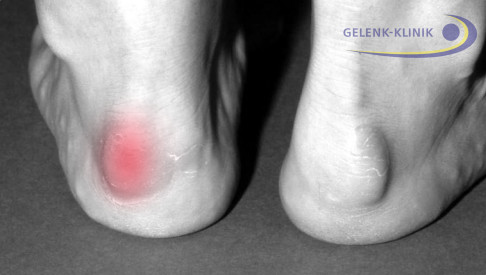

Durch den knöchernen Anbau am Fersenbein kommt es in diesem Bereich zu Druckstellen infolge des Schuhkonflikts. Reizungen entstehen sowohl an der Achillessehne als auch am Schleimbeutel zwischen Achillessehne und Fersenbein (Bursa subachillea). Durch das schmerzhafte Reiben an den Schuhen entstehen starke Fußschmerzen. Diese können als Anlaufschmerzen oder im späteren Verlauf der Erkrankung auch dauerhaft beim Gehen auftreten.

Nach einiger Zeit in Bewegung kann der Fersenschmerz wieder zurückgehen. Überehrgeizige Sportler machen sich das zu Nutze, indem sie beim Training durch den Schmerz "hindurch" trainieren. Dies ist sehr schädlich, weil die Überlastung und Reizung der Weichgewebe immer weiter zunimmt. Die Haglundferse kann einen Fuß oder beide Füße gleichzeitig betreffen.

Zunächst beurteilt der Arzt Aussehen und Beweglichkeit des Fußes in einer klinischen Untersuchung. Die Vorwölbung der Haglundexostose ist meist mit bloßem Auge sichtbar. Häufig berichten Patienten zudem von starken Fersenschmerzen und Beschwerden beim Gehen, die dem Arzt weitere Hinweise liefern. Eine radiologische Untersuchung sichert die Blickdiagnose ab. Das seitliche Röntgenbild des Fußes zeigt einen deutlichen Knochenvorsprung (Überbein oder Exostose) im Bereich der Ferse. Mögliche Kalkablagerungen in der Achillessehne als Folge der Reizung sind ebenfalls im Röntgenbild sichtbar.